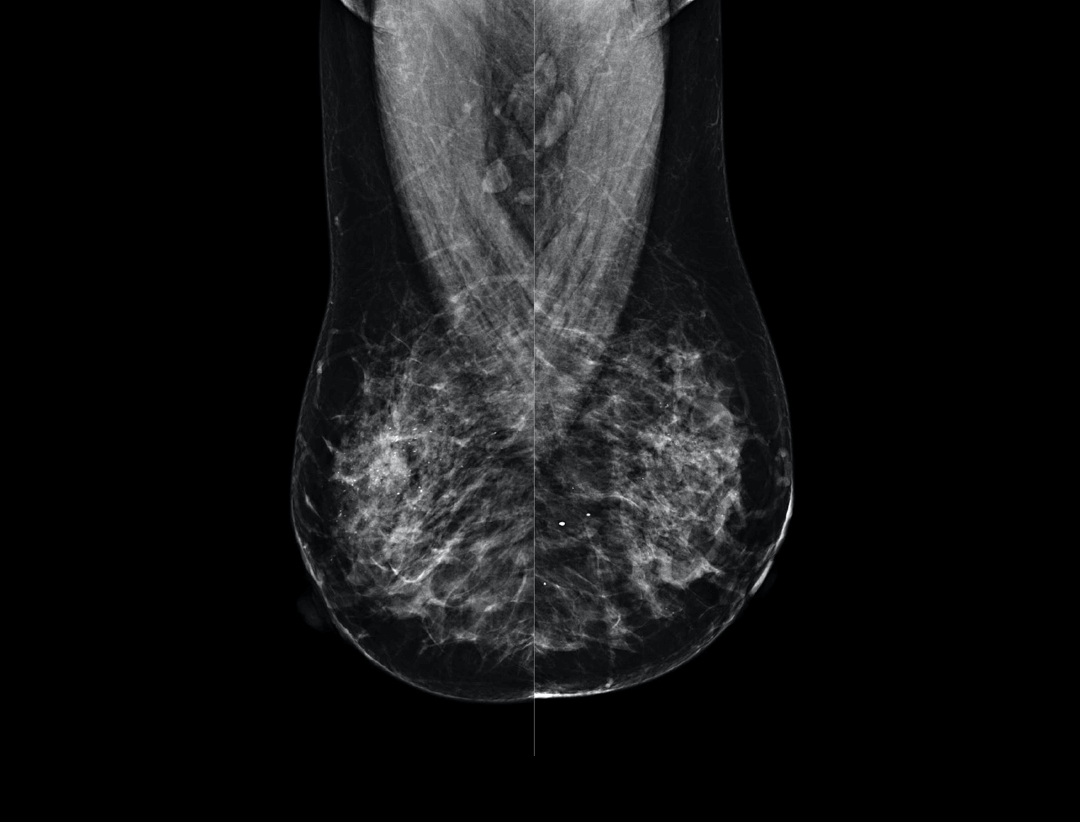

Large coverage amorphous-silicon (a-Si) flat panel detector featuring an optimized active matrix array provides high spatial resolution and high image acquisition speed at a lower dose.

High performance tungsten target X-ray tube offers high resolution image for both dense and fatty breast densities.

Intelligntly detects breast density and thickness, then auto selects the appropriate filter combination.